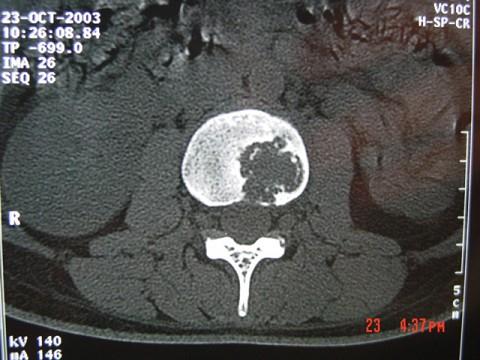

问题 男,33岁,有午后发热,夜间盗汗等,腰部疼痛,活动时加重,休息后减轻,请结合所提供图像,选择最佳答案 ( )

选项 A、骨巨细胞瘤 B、骨髓瘤 C、腰椎骨转移 D、腰椎退行性变 E、腰椎结核

答案 E